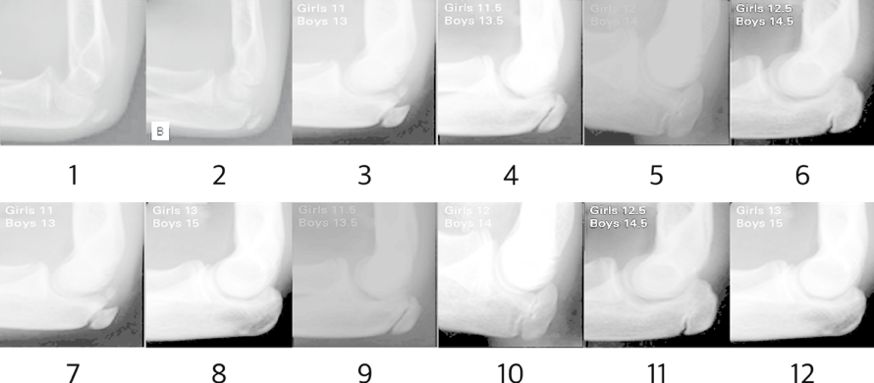

To compare the reference X-ray images, we selected the age of bone presented in the 10 elbow x-ray images of A COMPARISON OF THE SIMPLIFIED OLECRANON AND DIGITAL METHODS OF ASSESSMENT OF SKELTAL MATURITY DURING THE PUBERTAL GROWTH SPURT\endnoteCanavese, F., et al. "A comparison of the simplified olecranon and digital methods of assessment of skeletal maturity during the pubertal growth spurt." The bone & joint journal 96.11 (2014): 1556-1560. At this time, the original images were excluded from the learning images to be used as evaluation images at the end of the research. Also, elbow x-ray images of 10 and 11 year old boys missing from ’ A comparison of the simplified olecranon and digital methods of assessment of skeltal maturity during the pubertal growth spurt’ were added as reference images of elbows of 10 and 11 year old boys presented in STUDY OF SECONDARY OSSIFICATION CENTERS OF THE ELBOW IN THE BRAZILIAN POPULATION\endnoteMiyazaki, Cesar Satoshi, et al. "Study of secondary ossification centers of the elbow in the brazilian population." Acta ortopedica brasileira 25.6 (2017): 279-282. After this procedure, the reference X-ray image was finally defined as shown in Fig 2.

Refer to caption

Figure 2: Test Data for Elbow Image